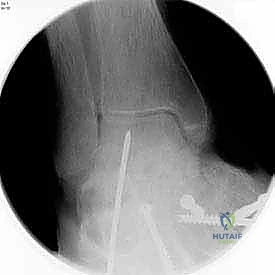

3. التصوير الشعاعي (X-rays): صور أشعة سينية أثناء الوقوف (Weight-bearing) لتقييم زوايا العظام ودرجة انهيار المفاصل.

بعد التأكد من الوضعية المثالية للعظام، يتم تثبيتها بقوة باستخدام مسامير معدنية مجوفة من التيتانيوم (Cannulated Screws) أو شرائح معدنية خاصة. يتم إدخال المسامير تحت توجيه الأشعة السينية المباشرة (Fluoroscopy) داخل غرفة العمليات لضمان الدقة المتناهية. هذه المسامير تضغط العظام معاً وتمنع أي حركة حتى يحدث الالتئام التام.